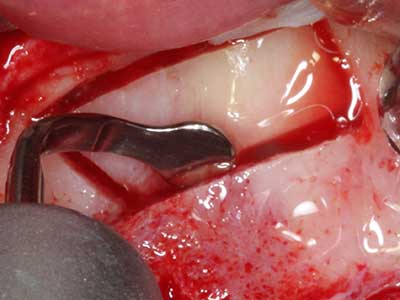

Fig. 20: La tapa ósea extraída se readapta y se fija mediante un tornillo para osteosíntesis (KLS Martin, Tuttlingen).

Fig. 19: Zona operada después de neurolisis y eliminación del osteomo.